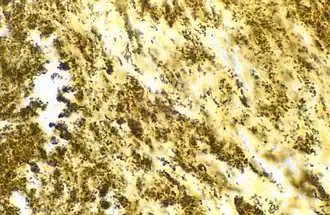

![]() Bartonella henselae бациллы в ткани сердечного клапана пациента с эндокардитом и отрицательным посевом крови: бациллы выглядят как чёрные гранулы. | |